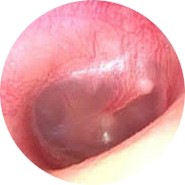

| TEED 2 |

Diffuse redness and retraction of tympanic membrane, plus slight hemorrhage within the tympanic membrane. |

|